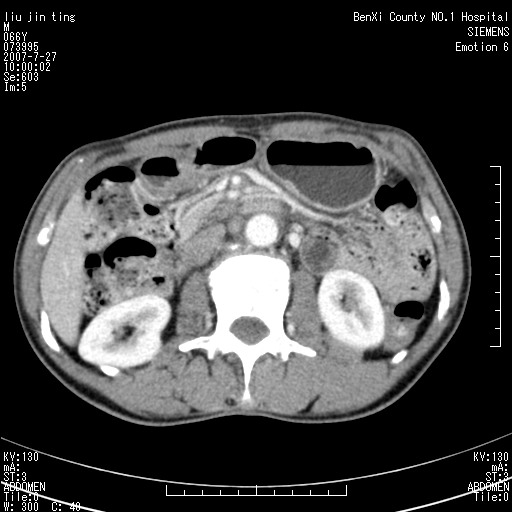

腹痛,背痛,无恶心呕吐,不黄,彩超示胰腺钩癌,ct扫描病灶平扫30-40hu,增强后动脉期40--60hu,静脉期50-68hu,真的是钩突上的么?您要试一试么?

动脉期

静脉期